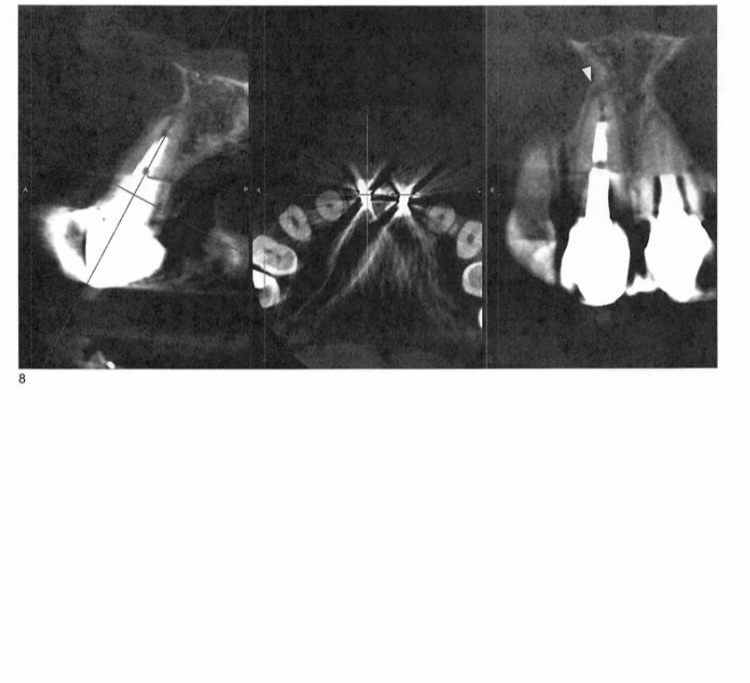

通院している歯医者さんは日本人の先生で、以前にも同様の古いメタルコアの患者さんを扱ったことがあるとの事で、 まず根管治療医を紹介されました。そこで3D/CTを撮ったところ、「入っているクラウンのメタルがかなり大きいので歯の冠部、根部の構造が損なわれている。一方の歯には充填が足りていないスぺースがあり、もう一方には少しの炎症が見られる、 上顎洞に炎症性粘膜の肥厚が認められるが副鼻腔炎は視認できない」との結果でした。

※その時の画像を添付します。

根管治療の先生からは「画像では歯のスペースが小さいので、開けてみたら使える歯が残っていない、あるいは再根管治療をしても長く持たない可能性も低くはない。インプラントを考えてみては」と言われました。

画像1IMG_6505.jpeg 画像2IMG_6504.jpeg